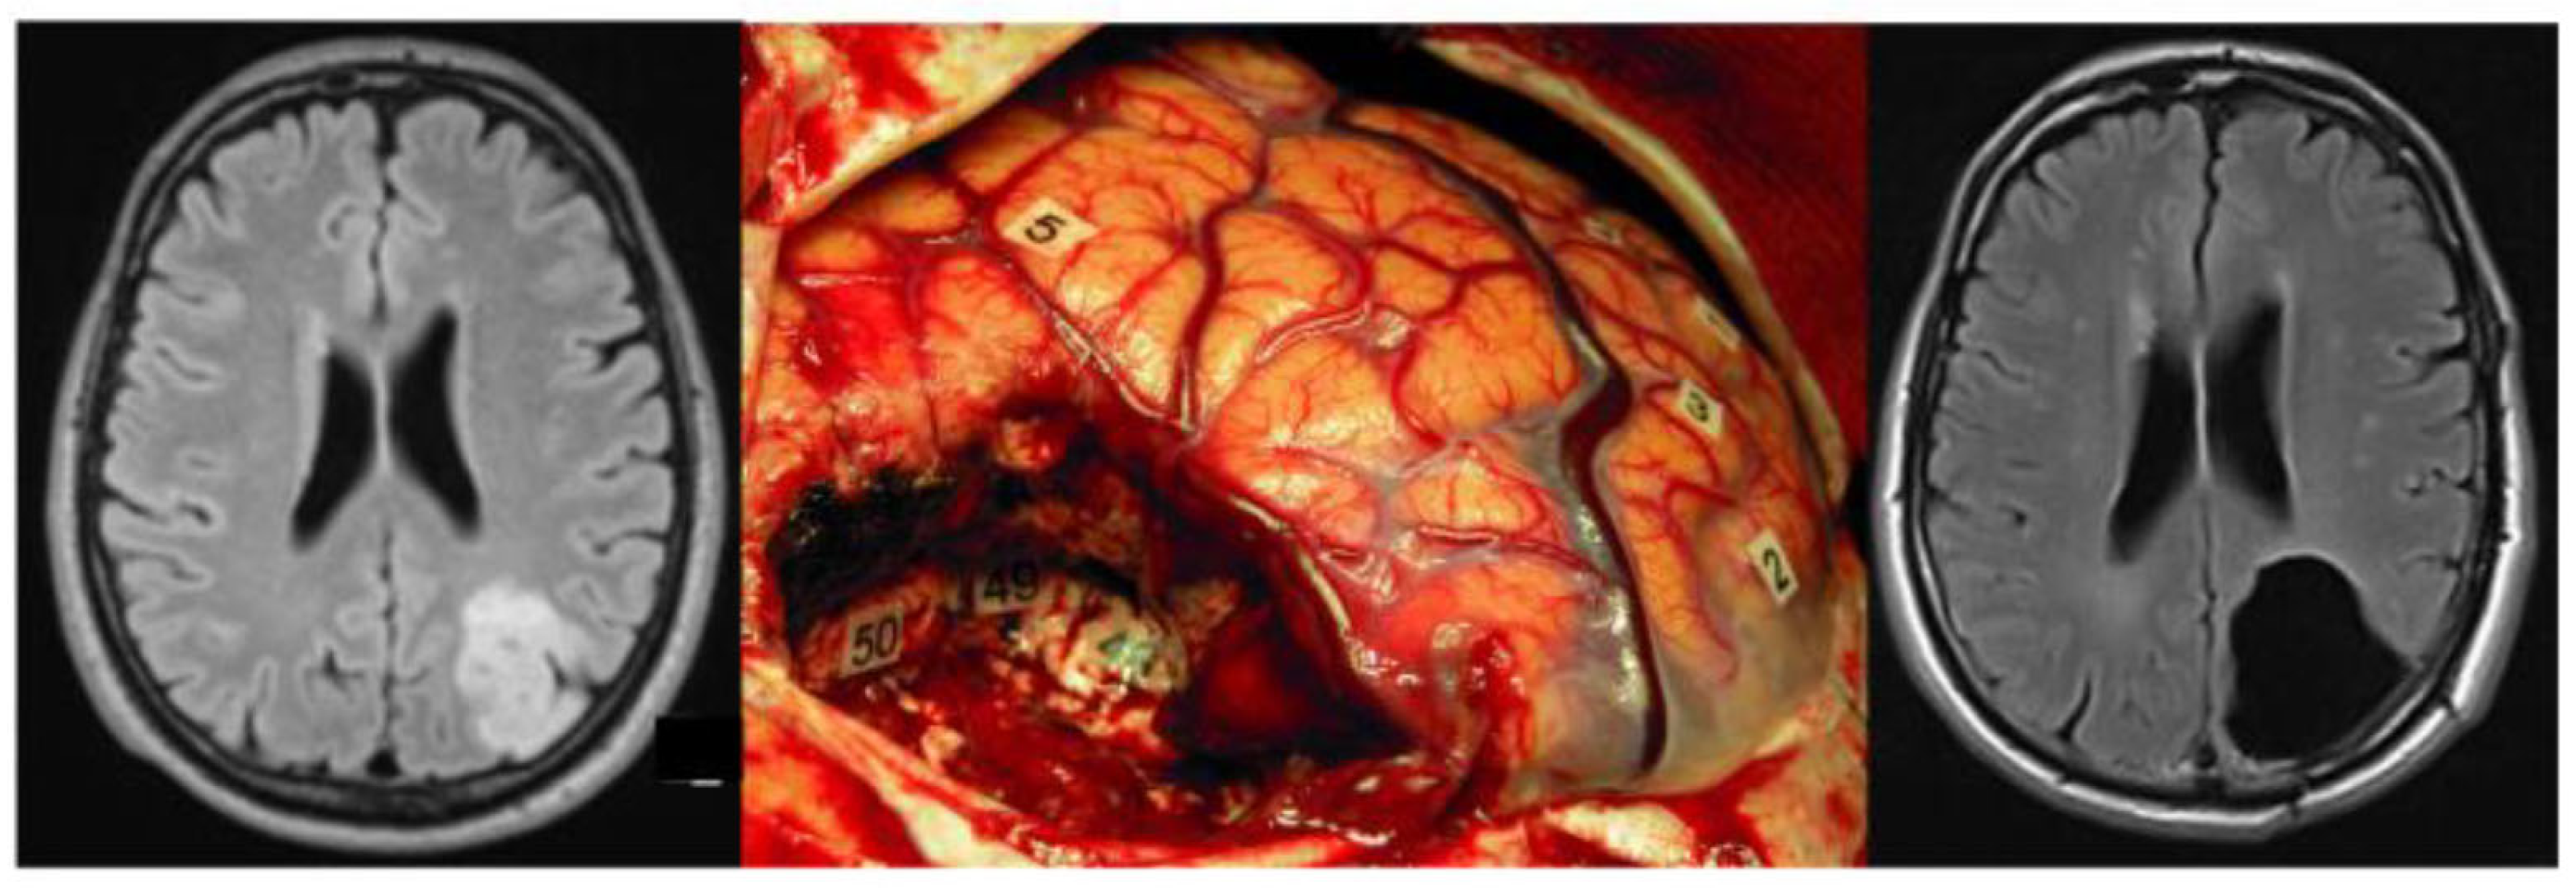

4. PTZ Recognition Supports Supratotal Resection and Vice Versa